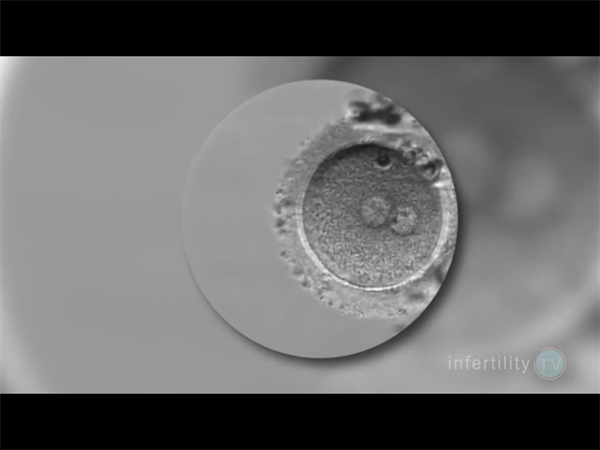

临床中,我们常遇到因“过度焦虑”或“盲目试孕”延误时机的案例,事实上 科学评估生育力是高效备孕的第一步...